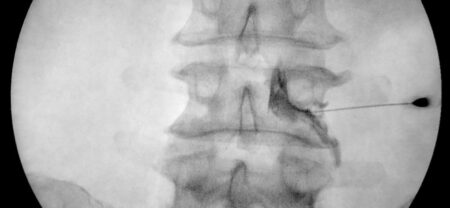

Se suelen hacer guiados mediante ecografía, rayos x o por anatomía.